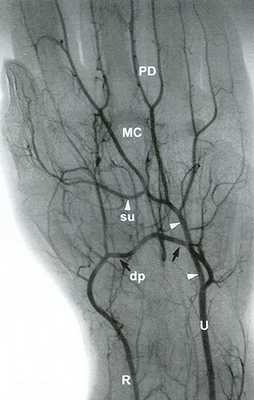

Рис. 14.5. Лучевая артерия (R) заканчивается глубокой ладонной дугой (dp - черные стрелки). Локтевая артерия (V) заканчивается поверхностной ладонной дугой (su - белые головки стрелок). Поверхностная и глубокая дуги обычно сообщаются посредством коммуникантных сосудов, что отражено на ангиограмме. Пястная артерия (МС; также называемая общей ладонной пальцевой артерией или дорсальной пястной артерией) и ладонная пальцевая (РВ) артерия являются ветвями поверхностной и глубокой дуг.